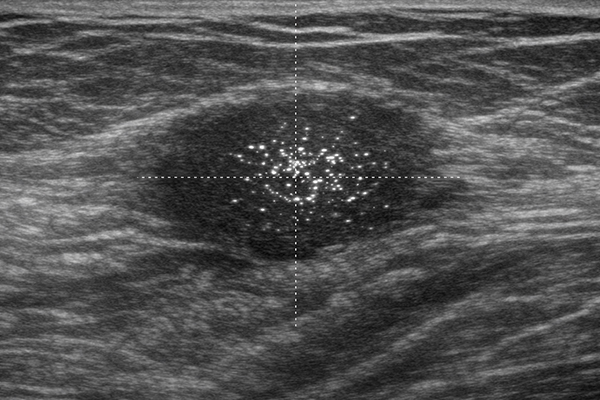

미세석회화는 하얗고 미세한 점들이 군집 형태로 관찰되는 석회화를 의미합니다.

결절을 동반하지 않은 미세석회는

유방초음파에서는 보이지 않는 경우가 많으며,

유방촬영술을 통해 발견됩니다.

미세석회화는 초기 유방암을 확인할 수 있는 중요한 소견입니다.